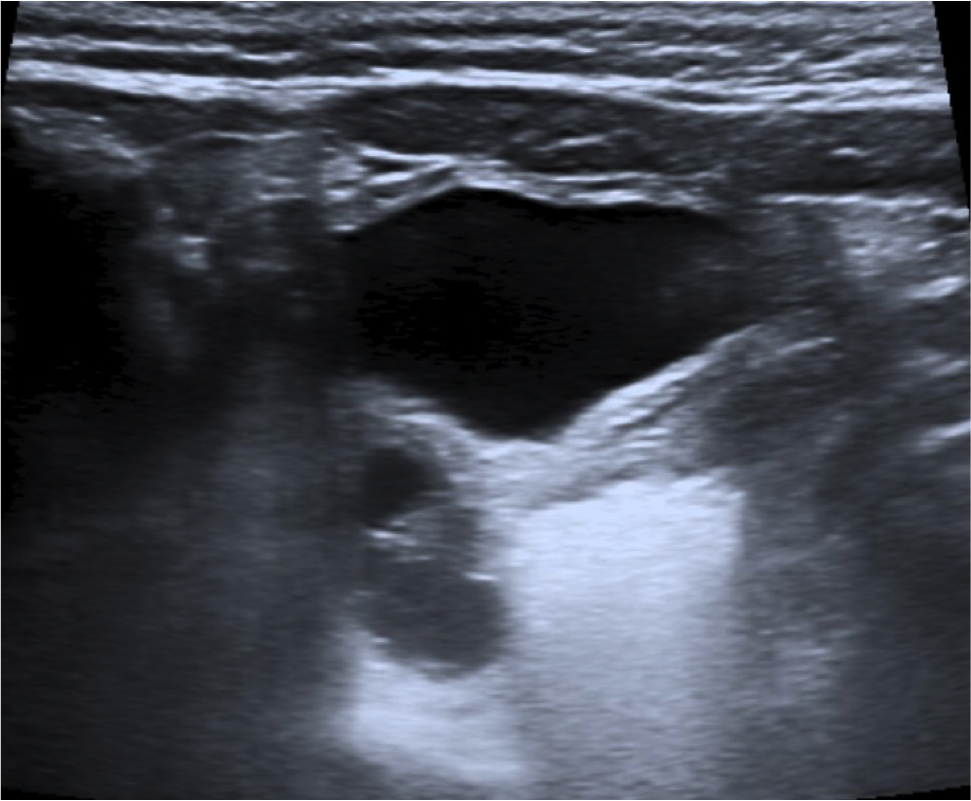

- La ecografía es la técnica de elección (ecógrafo de alta frecuencia)

- El ovario se identifica como una masa con quistes periféricos que representan los folículos.

- La mayoría de estas hernias son de tamaño inferior a 3 cm.

Como ya comentamos, el diagnóstico precoz es importante para evitar que la hernia se complique. Si la torsión del ovario se produce, el compromiso primero venos y linfático y luego arterial produciran a los signos de inflamación , congestión y finalmente isquemia. Los pacientes pueden presentar clínica y signos de irritabilidad, dolor, vómitos, gangrena y necrosis tisular. La imágen ecográfica de torsión ovárica es la de un ovario agrandado con quístes, ecogenicidad heterogénea, sin captación de flujo Doppler color y repercusión de la grasa adyacente.